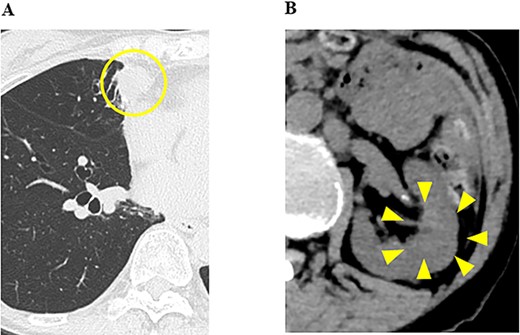

Ten months after the start of lenvatinib, CT showed a decrease in the sizes of pulmonary metastases (Fig. 3A) and renal metastasis (Fig. 3B) (tumor reduction rate: 45%). Remnant thyroid resection was performed and followed by RAI therapy with 100 mCi. In 131I scintigraphy, some lung metastases showed radioiodine uptake, whereas others did not. Radioiodine uptake was also observed in the left renal tumor, but not in the right kidney (Fig. 4A); therefore, the left renal tumor was finally confirmed as renal metastasis of PTC. Since the sizes of pulmonary and renal metastases both increased after the RAI therapy (tumor growth rate: 71%) (Fig. 4B), the administration of lenvatinib was resumed from a dose of 4 mg/day. After resuming lenvatinib, she has been in SD status for 6 months.

CT images of the chest and abdomen 10 months after the start of the administration of lenvatinib, and (A) pulmonary metastases decreased in size; (B) the size of the renal tumor decreased and the tumor plug disappeared.